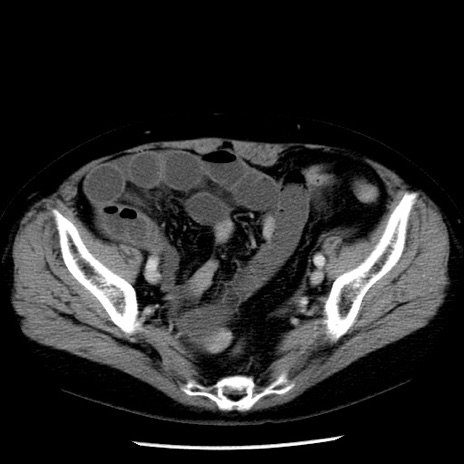

症例13(横断像)

【症例】70歳代女性

【主訴】腹痛、嘔吐

【現病歴】15時間程前(昨晩)より腹痛あり。今朝になっても症状の改善なく、嘔吐あり。腹痛も増悪あり、救急外来受診。

【既往歴】子宮癌全摘術後

【身体所見】意識清明、BP 121/72mmHg、P 74bpm、SpO2 100%(RA)、腹部:平坦・軟、腸雑音ほぼ聴取せず。下腹部・心窩部・臍左上に圧痛あり。反跳痛なし。

【データ】WBC 10600、CRP 0.15